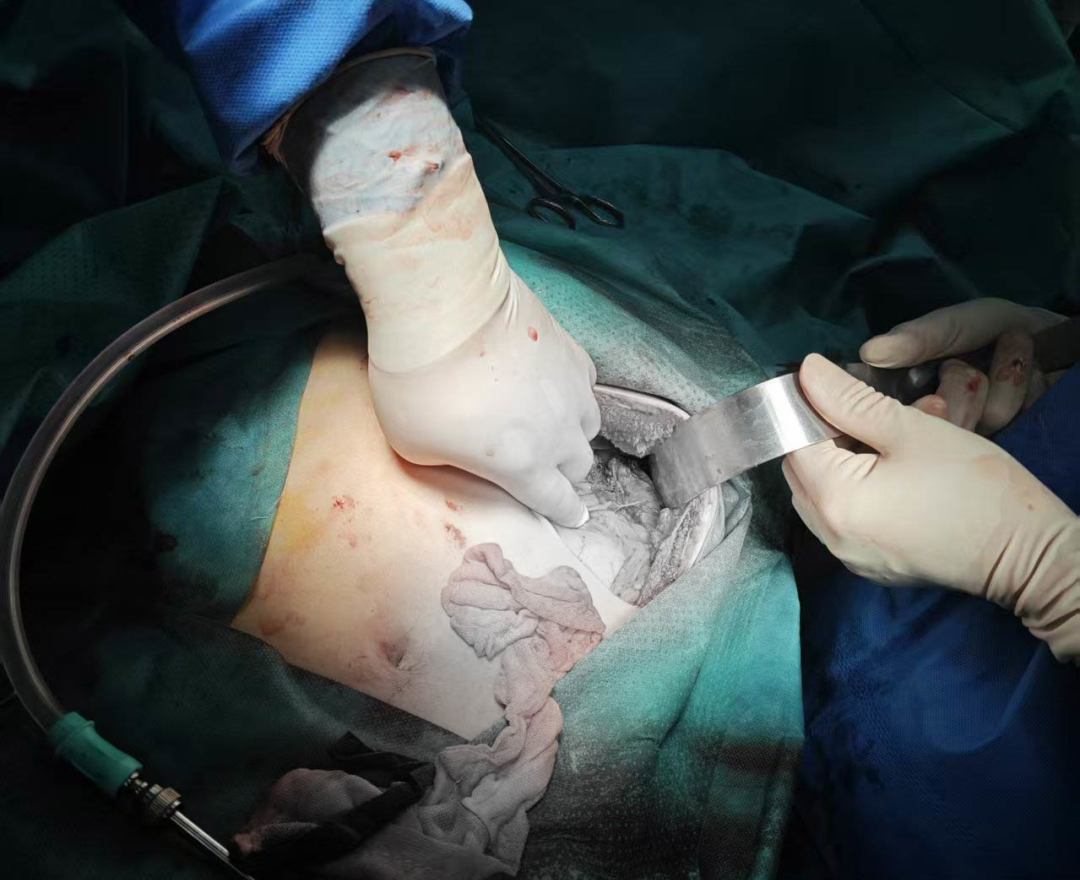

2025年5月31日清晨,23岁的李先生(化名)因骑电动车不慎摔倒导致左侧季肋区受伤、创伤性脾破裂,失血性休克。经我院创伤中心团队紧急施救,成功实施脾修补手术。